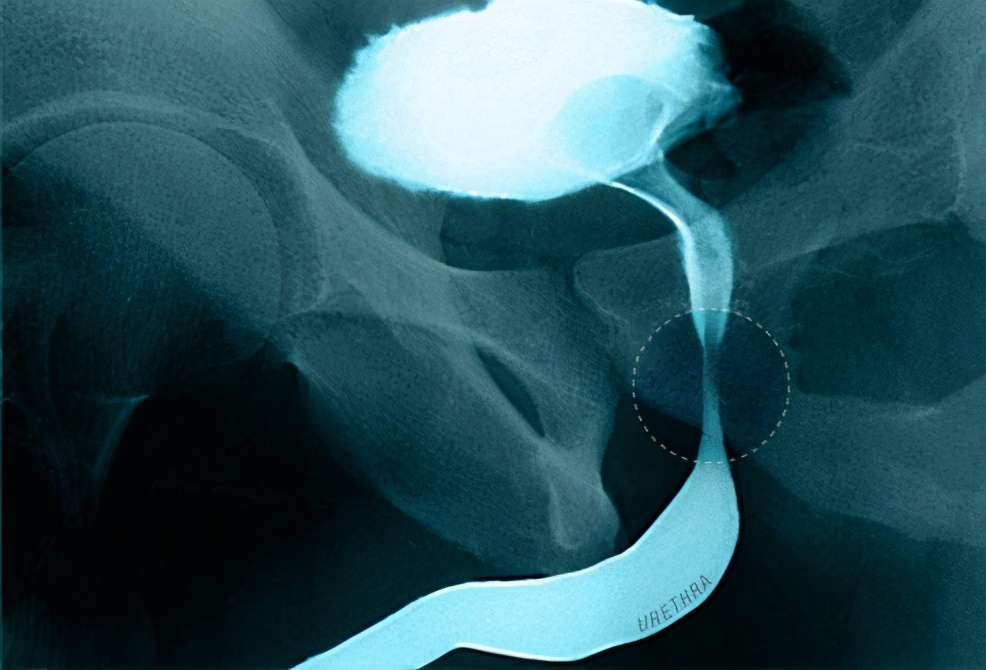

当前列腺增大到完全堵塞尿道(如图)或出现膀胱感染的时候人就会出现无法排尿的症状。膀胱肌肉也可能变得太弱而不能通过收缩将尿液挤出。

不管是哪种原因,这都可能会损伤肾脏,因此一旦发现无法排尿的情况,一定立即就医以预防肾脏损伤。如果是突然无法排尿,请拨打120或到急诊室立即就诊。